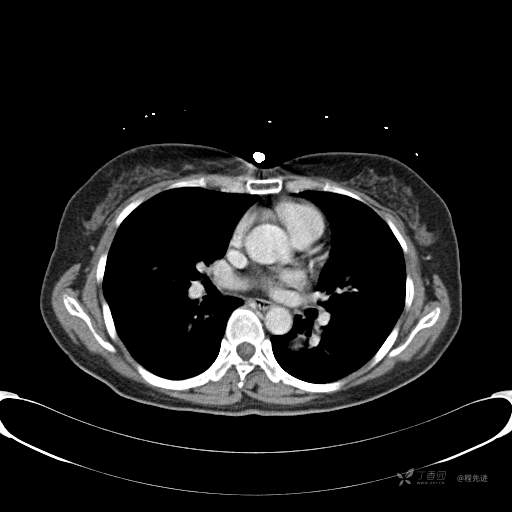

患者性别:女

患者年龄:57岁

简要病史:体检发现

CT增强

平扫CT值约40HU(未上传图像),增强后动脉期CT值约70HU,静脉期CT值约97HU。

肺硬化性血管瘤 (20)